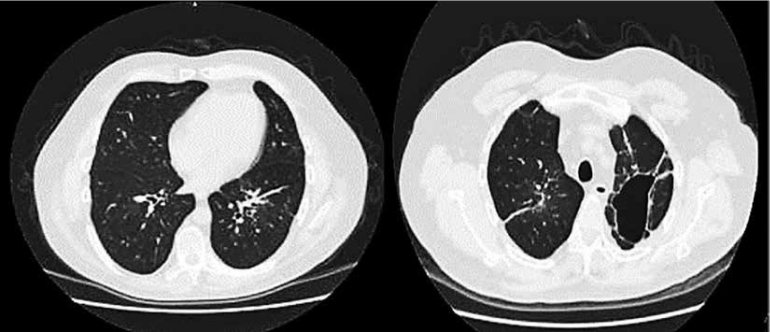

Se prescribe tratamiento inmunomodulador (gammaglobulinas) a dosis de 0,4 g/kg/dia por 5 días consecutivos. Paciente a la semana de inicio de gammaglobulinas, presento mejoría clínica significativa, con remisión progresiva de dificultad respiratoria por lo que se dio de alta para continuar tratamiento ambulatorio. Acudió al centro hospitalario después de un mes de tratamiento donde obtenemos un control tomografíco simple de tórax, en la que se observa campos pulmonares sin lesiones consolidativas en comparación con el estudio de ingreso. (FIGURA 2)